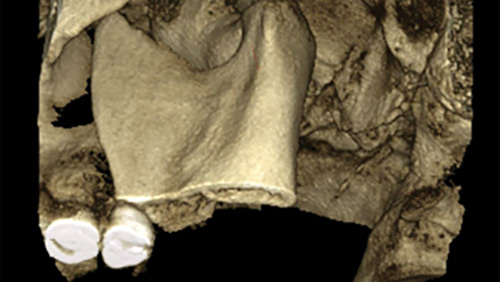

Multidisciplinary approaches to restoring vertical dimension of occlusion: Two clinical case studies of collapsed bite and symptoms of TMJ pain dysfunction syndrome

Abstract Tooth wear due to aging is a natural physiological process that generally does not negatively impact individuals unless exacerbated by parafunctional habits such as bruxism or congenital anomalies. This paper explores the implications of the loss of vertical dimension of occlusion (VDO) and its effects on the stomatognathic system. Symptoms of temporomandibular joint (TMJ) … Read more